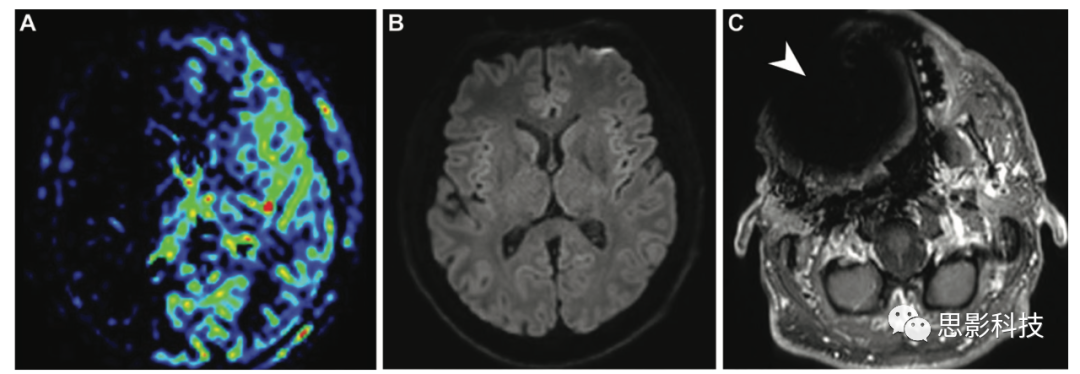

一位56歲健康男性,由于右側(cè)上牙弓上種植金屬牙體造成的標(biāo)記偽影無效。(A)ASL圖顯示右側(cè)頸內(nèi)動(dòng)脈低信號(hào),類似于低灌注。(B)彌散加權(quán)磁共振圖像未顯示受限區(qū)域。(C)軸位高分辨率增強(qiáng)T1加權(quán)MRI顯示右側(cè)上頜金屬牙引起的易感性偽影(箭頭)。頸部和顱內(nèi)MR血管造影(未顯示)均正常。

感染 腦膿腫在中腔及周圍水腫區(qū)的ASL信號(hào)降低,邊緣強(qiáng)化的信號(hào)增強(qiáng)(18)。據(jù)報(bào)道,在硬膜外膿腫和其他感染性疾病,如皰疹性腦炎,可能繼發(fā)于靜脈受壓或局部大腦調(diào)節(jié)機(jī)制障礙,顯示皮質(zhì)ASL信號(hào)強(qiáng)度增加。

18 腦膿腫,9歲兒童癲癇發(fā)作5天。(AB)軸位增強(qiáng)T1加權(quán)像(A)和彌散加權(quán)像(B)顯示左側(cè)額葉局灶性病變,呈環(huán)形強(qiáng)化,彌散受限,表明膿腫。(C)ASL MRI顯示病灶核心的低CBF,周圍有水腫。邊緣強(qiáng)化顯示信號(hào)增強(qiáng)。

癲癇 ASL MRI可以幫助評(píng)估癲癇,其結(jié)果已被證明與SPECTPET研究結(jié)果一致。ASL MRI可以識(shí)別潛在病灶,有助于鑒別診斷。癲癇發(fā)作的機(jī)制、時(shí)機(jī)和慢性化等因素可能會(huì)影響ASL成像。因此,關(guān)于患者的臨床病史和成像時(shí)表現(xiàn)是至關(guān)重要的。在發(fā)作期和急性發(fā)作間歇期,由于神經(jīng)元活動(dòng)增加,活躍的致癇區(qū)顯示出高血流量(19)。在慢性發(fā)作間歇期,由于活躍度和功能降低以及不成比例的萎縮,致癇區(qū)可能表現(xiàn)出低血流量

19 一名54歲男性癲癇發(fā)作30分鐘后的早期發(fā)作后狀態(tài)。(A,B)冠狀面FLAIR(A)和軸位高分辨率增強(qiáng)T1加權(quán)(B)顯示左側(cè)海馬和鉤回(箭頭)呈高信號(hào),略有強(qiáng)化。(C)ASL表明相關(guān)區(qū)域(箭頭)的高灌注,有助于識(shí)別潛在致癇灶,并隨著時(shí)間的推移有不同的表現(xiàn)。